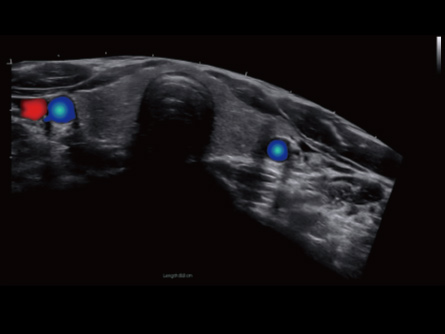

Experimenta la excelencia en radiología con los equipos de ultrasonido de CHISON. Nuestros dispositivos de alto rendimiento ofrecen imágenes de precisión y características avanzadas, satisfaciendo las demandas de los radiólogos de todo el mundo. Desde la visualización clara de tejidos blandos hasta escaneos rápidos, nuestras máquinas optimizan el flujo de trabajo, garantizando la precisión diagnóstica. Explora nuestras soluciones de ultrasonido de radiología mejor valoradas para una atención superior al paciente y satisface las necesidades de tus pacientes con confianza.

Dedicated Features